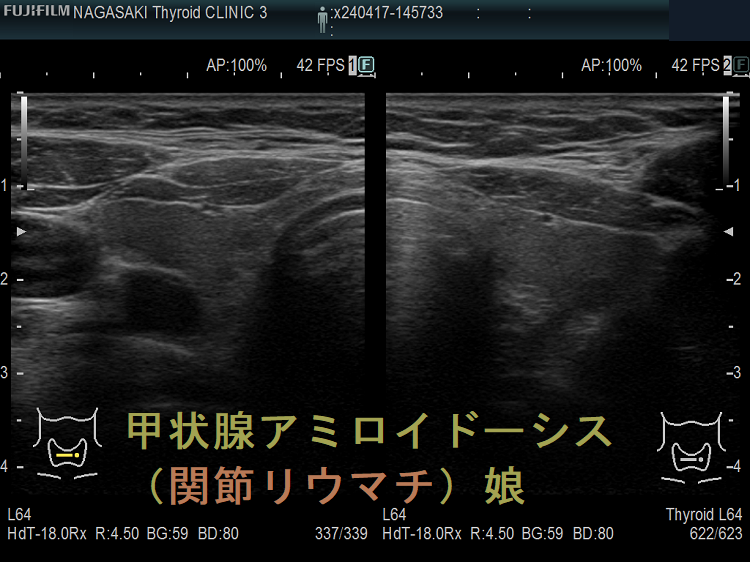

甲状腺アミロイドーシス(関節リウマチ)母娘

甲状腺アミロイドーシスの細胞診